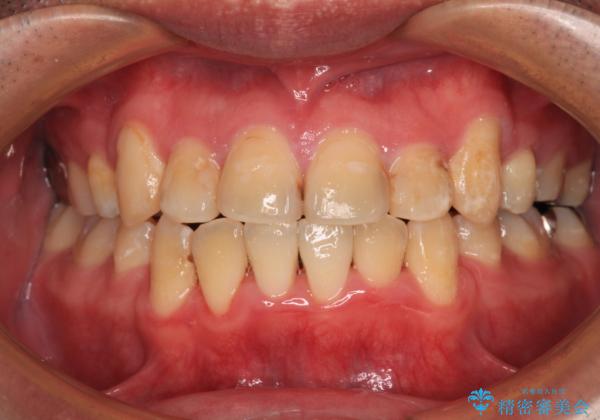

- 上下の八重歯やデコボコを気にして来院された患者様です。

上下ともに八重歯が顕著であったので、上下左右第一小臼歯4本を抜歯し、ワイヤー装置にて矯正治療を行うこととしました。

デコボコが強いことが原因で歯間部に汚れが溜まりやすい状態でしたが、矯正前にできる限り汚れが少なくなるようにブラッシングなどの指導を行い、口腔状態が改善された後にワイヤー装置を装着することとしました。